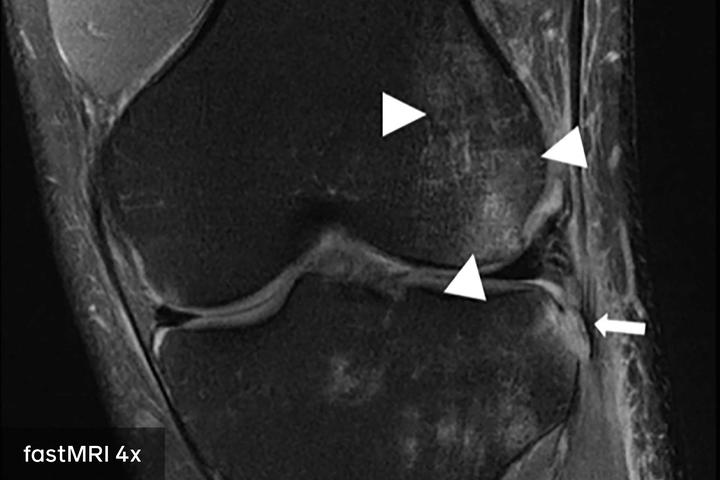

W ramach trwającego od dwóch lat projektu, badaczom udało się opracować rozwiązanie AI, które pozwala na wygenerowanie dokładnego skanu MRI na podstawie ¼ danych potrzebnych do stworzenia standardowego obrazu.

Rezultaty pierwszych badań klinicznych, które zostaną opublikowane na łamach American Journal of Roentgenology dowiodły, że obrazy rezonansu magnetycznego wspieranego opracowaną w ramach projektu metodą, można stosować zamiennie z obrazami uzyskiwanymi w zwykłym rezonansie magnetycznym.

Zespół fastMRI użył zupełnie innego sposobu tworzenia obrazu – takiego, który wymaga znacznie mniej surowych danych. Naukowcy zbudowali sieć neuronową i wyszkolili ją przy użyciu największego na świecie zbioru danych rezonansu magnetycznego kolana o otwartym kodzie źródłowym, który został stworzony i udostępniony przez NYU Langone Health w ramach inicjatywy fastMRI.

Zespół badawczy fastMRI usunął około trzech czwartych surowych danych w każdym skanie, a następnie wprowadzał pozostałe informacje do modelu AI. Model nauczył się wtedy generować kompletne obrazy z ograniczonych danych. Co ważne, obrazy wytworzone przez model AI nie wyglądały jak zwykłe MRI.

Obrazy generowane przez sztuczną inteligencję pasowały do obrazu utworzonego przez standardowy powolny proces MRI. Wyobraź sobie, że bierzesz tylko 250 elementów układanki z 1000 elementów, a następnie układasz cały obraz w sposób, który nie tylko wygląda wiarygodnie; dokładnie pasuje do całej układanki pokazanej na pudełku. To przybliżone przybliżenie tego, co zespół fastMRI był w stanie zrobić ze swoim modelem.